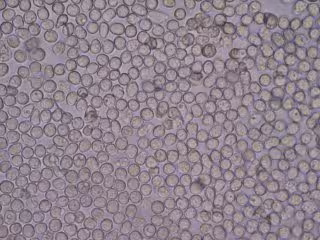

Archivo - Glóbulos Blancos

Archivo - Glóbulos Blancos - BOBJGALINDO/WIKIMEDIA COMMONS - Archivo